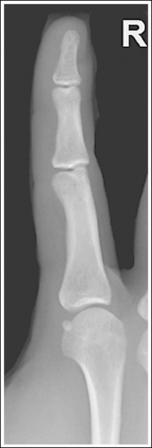

See Figure 4-1 and Box 4-2.

The finger demonstrates a PA projection. The soft tissue width and midpoint concavity are the same on both sides of the phalanges.

• Finger rotation is controlled by the amount of palm pronation. A PA projection is accomplished when the palm is positioned flat against the IR (Figure 4-2).

• Detecting finger rotation. Because the thumb prevents the hand from rotating laterally, medial rotation is the most common rotation error. Take a few minutes to study a finger skeleton, and note how the midpoints of the phalanges have equal side concavity when it is placed in a PA projection. Also, note that the anterior surface is concave, whereas the posterior surface is slightly convex. As the skeleton is rotated internally or externally, the amount of concavity increases on the side toward which the anterior surface is rotated, whereas the side toward which the posterior surface rotates demonstrates less concavity. The same observations can be made about the soft tissue that surrounds the phalanges. More soft tissue thickness is present on the anterior (palmar) hand surface than on the posterior surface, so the side demonstrating the greatest soft tissue width on an image is the side toward which the anterior surface was rotated. Look for this midpoint concavity and soft tissue width variation to indicate rotation on a PA finger projection (see Image 1). Note on a hand skeleton that the second metacarpal is the longest of the finger digits and that the length decreases with each adjacent metacarpal. This information can be used to determine whether the patient's finger was internally or externally rotated for a mispositioned PA finger image. If the finger was externally rotated, the aspect of the phalanges demonstrating the greater midpoint concavity faces the thumb or longer metacarpal (see Image 1). If the finger was internally rotated, the aspect of the phalanges demonstrating the greater midpoint concavity faces the shorter metacarpal.

Image 1

No soft tissue overlap from adjacent digits is present.

• Spreading the fingers slightly prevents soft tissue overlapping from adjacent fingers. It is difficult to evaluate the soft tissue of an affected finger when superimposition of other soft tissue is present.

The interphalangeal (IP) and metacarpophalangeal (MP) joints are demonstrated as open spaces, and the phalanges are not foreshortened.

• Open IP and MP joint spaces and unforeshortened phalanges are demonstrated when the finger is fully extended and the central ray is perpendicular and centered to the proximal IP (PIP) joint. This finger positioning and central ray placement align the joint spaces parallel with the central ray and perpendicular to the IR, as shown in Figure 4-3, resulting in open joint spaces. It also prevents foreshortening of the phalanges, because their long axes are aligned parallel with the IR and perpendicular to the central ray. The alignment of the central ray and IR with the joint spaces and phalanges changes when the finger is flexed. In Figure 4-4, note how finger flexion causes the phalanges to foreshorten and be superimposed on the joint spaces (see Image 2).

Image 2

The soft tissue width and the concavity of the phalangeal midshafts on either side of the phalanx are not equal; the finger was rotated for the image. Because the side of the phalanges with the greater concavity and soft tissue width is facing the thumb, the finger was rotated externally for the image.

Place the finger in a PA projection by rotating the finger slightly internally. The hand should be flat against the IR.

The IP and MP joints are closed, and the distal and middle phalanges are foreshortened; the patient's finger was flexed.

Extend the patient's finger, and place the palm flat against the IR. If the patient is unable to extend the finger, image it in an AP projection, elevating the proximal metacarpals until the affected phalanx is parallel with the IR or the affected joint space is perpendicular to the IR (see Figure 4-5).